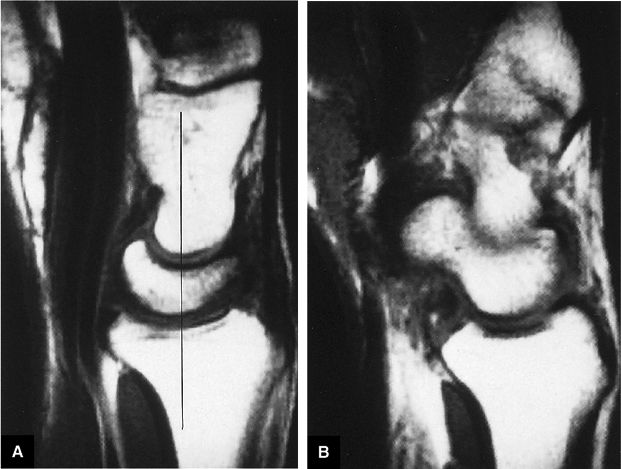

FIGURE 10.86 ● (A) With the wrist in a neutral position, there is normal colinear alignment of the capitate, lunate, and radius (black line). The normal capitolunate angle is between 0° and 30°. (B) When the scaphoid is positioned without dorsiflexion or palmarflexion, the normal scapholunate angle is between 30° and 60°.

|